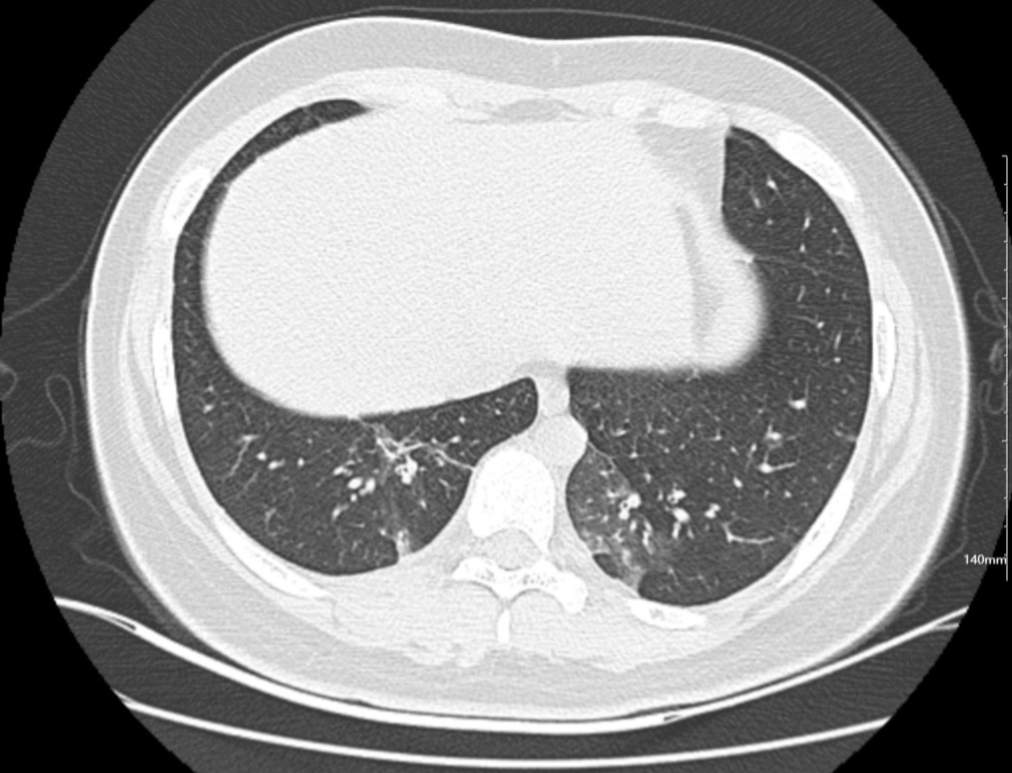

肺部CT:

百日咳肺炎CT 表现

支气管血管束增粗且伴 < 2 个肺叶的磨玻璃密度影, 多提示为单纯性百日咳肺炎。(下图:支气管血管束增粗, 两肺下叶基底段少许磨玻璃密度影)

如出现肺内支气管血管束增粗, 伴≥3 个肺叶斑片影、亚段性实变及支气管气象时, 提示患儿病情较重,可能合并其他感染。